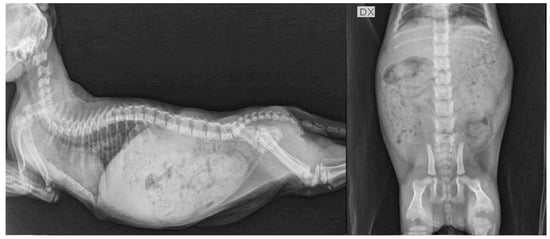

4. Clinical Cases

4.1. Case Description